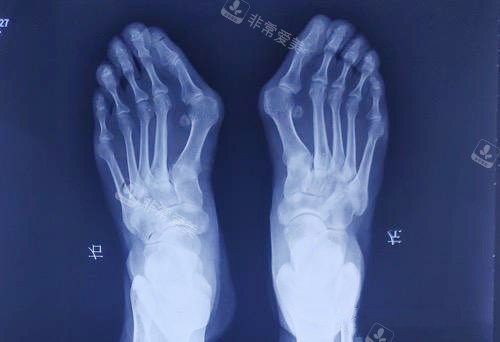

大脚骨拍片

虹桥医院拇外翻专科配备了一系列较高的医疗设备,如高精度的足部影像诊断设备,能够清晰地显示足部的骨骼结构和病变情况,为医生的诊断和治疗提供更准的依据。

大脚骨矫正术

大脚骨脚步骨头透视图